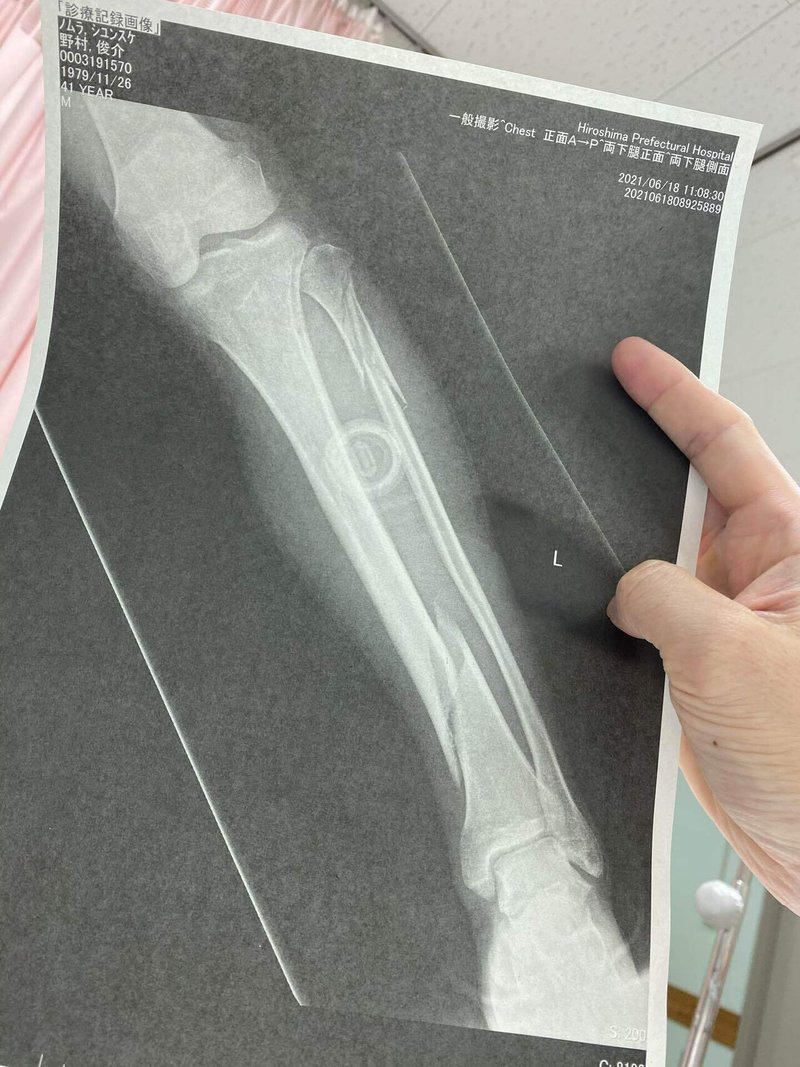

41歳2箇所骨折したおっさんの今 野村 俊介 Note